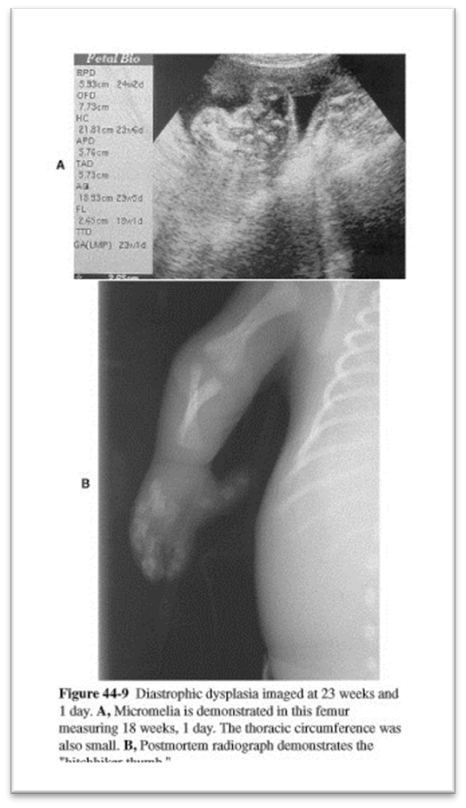

What is this image showing?

Diastrophic dysplasia